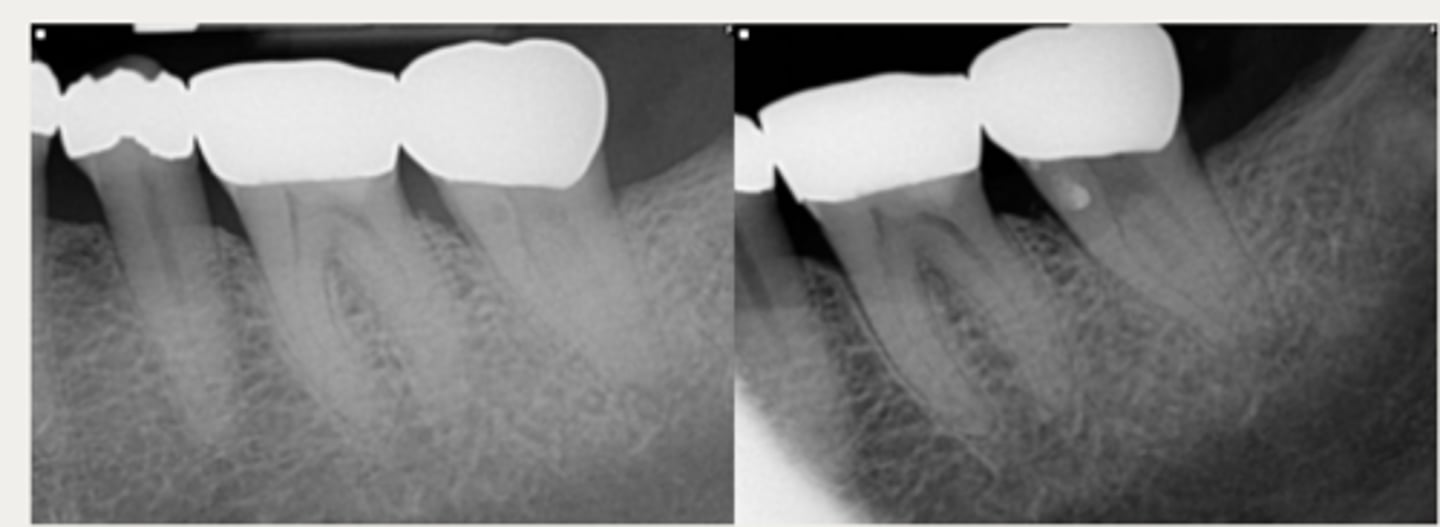

Lateral External Inflammatory Resorption

ID the type of resorption:

CLINICAL:

- History of trauma

- Pulpal Dx → necrotic

- Symptoms of apical periodontitis

- - May be tender to percussion and/or palpation

RADIOGRAPHIC:

- Radiolucent, crater shaped indentations on the root surface with adjacent bone loss and periradicular radiolucencies

Patient presents with history of trauma, does not respond to sensibility tests (necrotic pulp), is tender to percussion and/or palpation and has these radiographic findings. What is the most likely diagnosis?